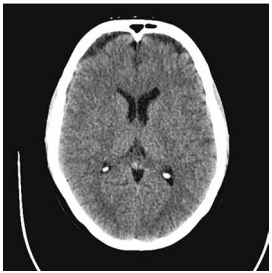

Paciente de 54 anos de idade, com história de febre, cefaleia intensa, vômitos e rebaixamento do nível de consciência há 24h. Glasgow 11; FC: 118 bpm; PA: 86 × 54 mmHg; Tax: 38,6 ºC; petéquias em tronco. SpO2: 96% em O2. Realizou-se a tomografia de crânio a seguir:

Enunciado 4482338-1 (Arquivo pessoal; imagem usada com autorização)

Qual é a prioridade terapêutica inicial?